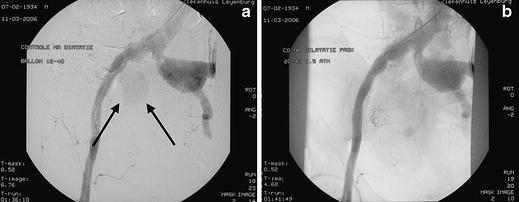

Ruptured aneurysms of the internal iliac artery (IIA) are rare and challenging to treat surgically. Due to their anatomic location they are difficult to operate on and perioperative morbidity is high. An endovascular approach can be helpful. We recently treated a patient with a ruptured IIA aneurysm in the interventional radiology suite with embolization of the side-branch of the IIA and placement of a covered stent in the ipsilateral common and external iliac arteries. A suitable stent-graft was not available initially and had to be brought in from elsewhere. An angioplasty balloon was temporarily placed across the ostium of the IIA to obtain hemostasis. Two hours later, the procedure was finished by placing the stent-graft.